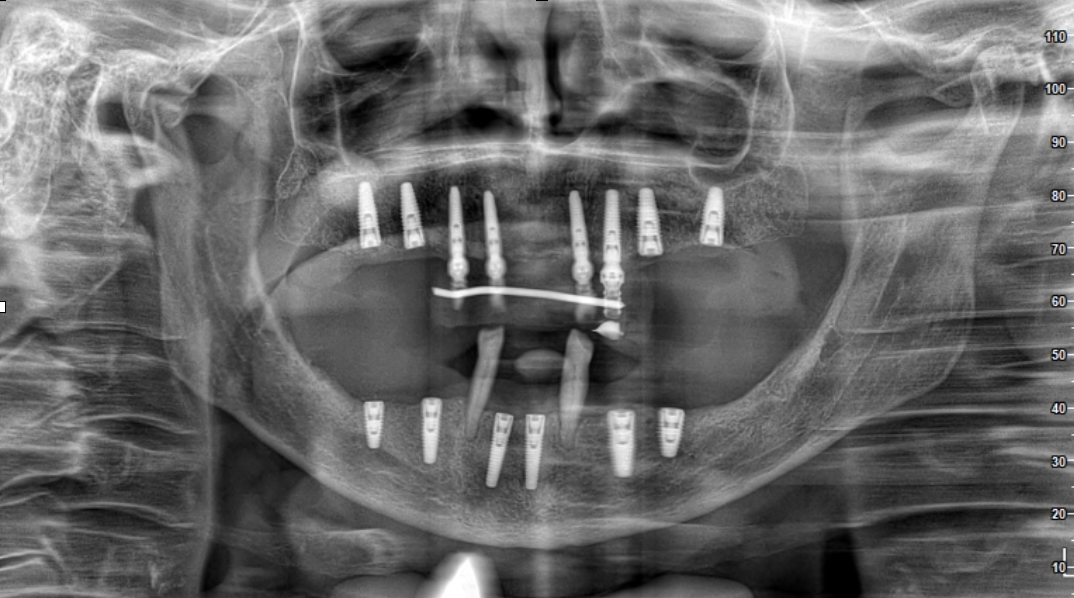

Estamos especializados en la regeneración ósea compleja mediante injertos:

• Injertos de Biomateriales (Artificiales): Para defectos pequeños.

• Injerto Óseo Autólogo (Hueso Propio): El estándar de oro para pérdidas severas, utilizando hueso de la mandíbula o cadera.

El tratamiento incluye Regeneración Ósea (4-5 meses de espera), Colocación del Implante, Integración Ósea (3-4 meses) y, finalmente, la Corona Protésica.